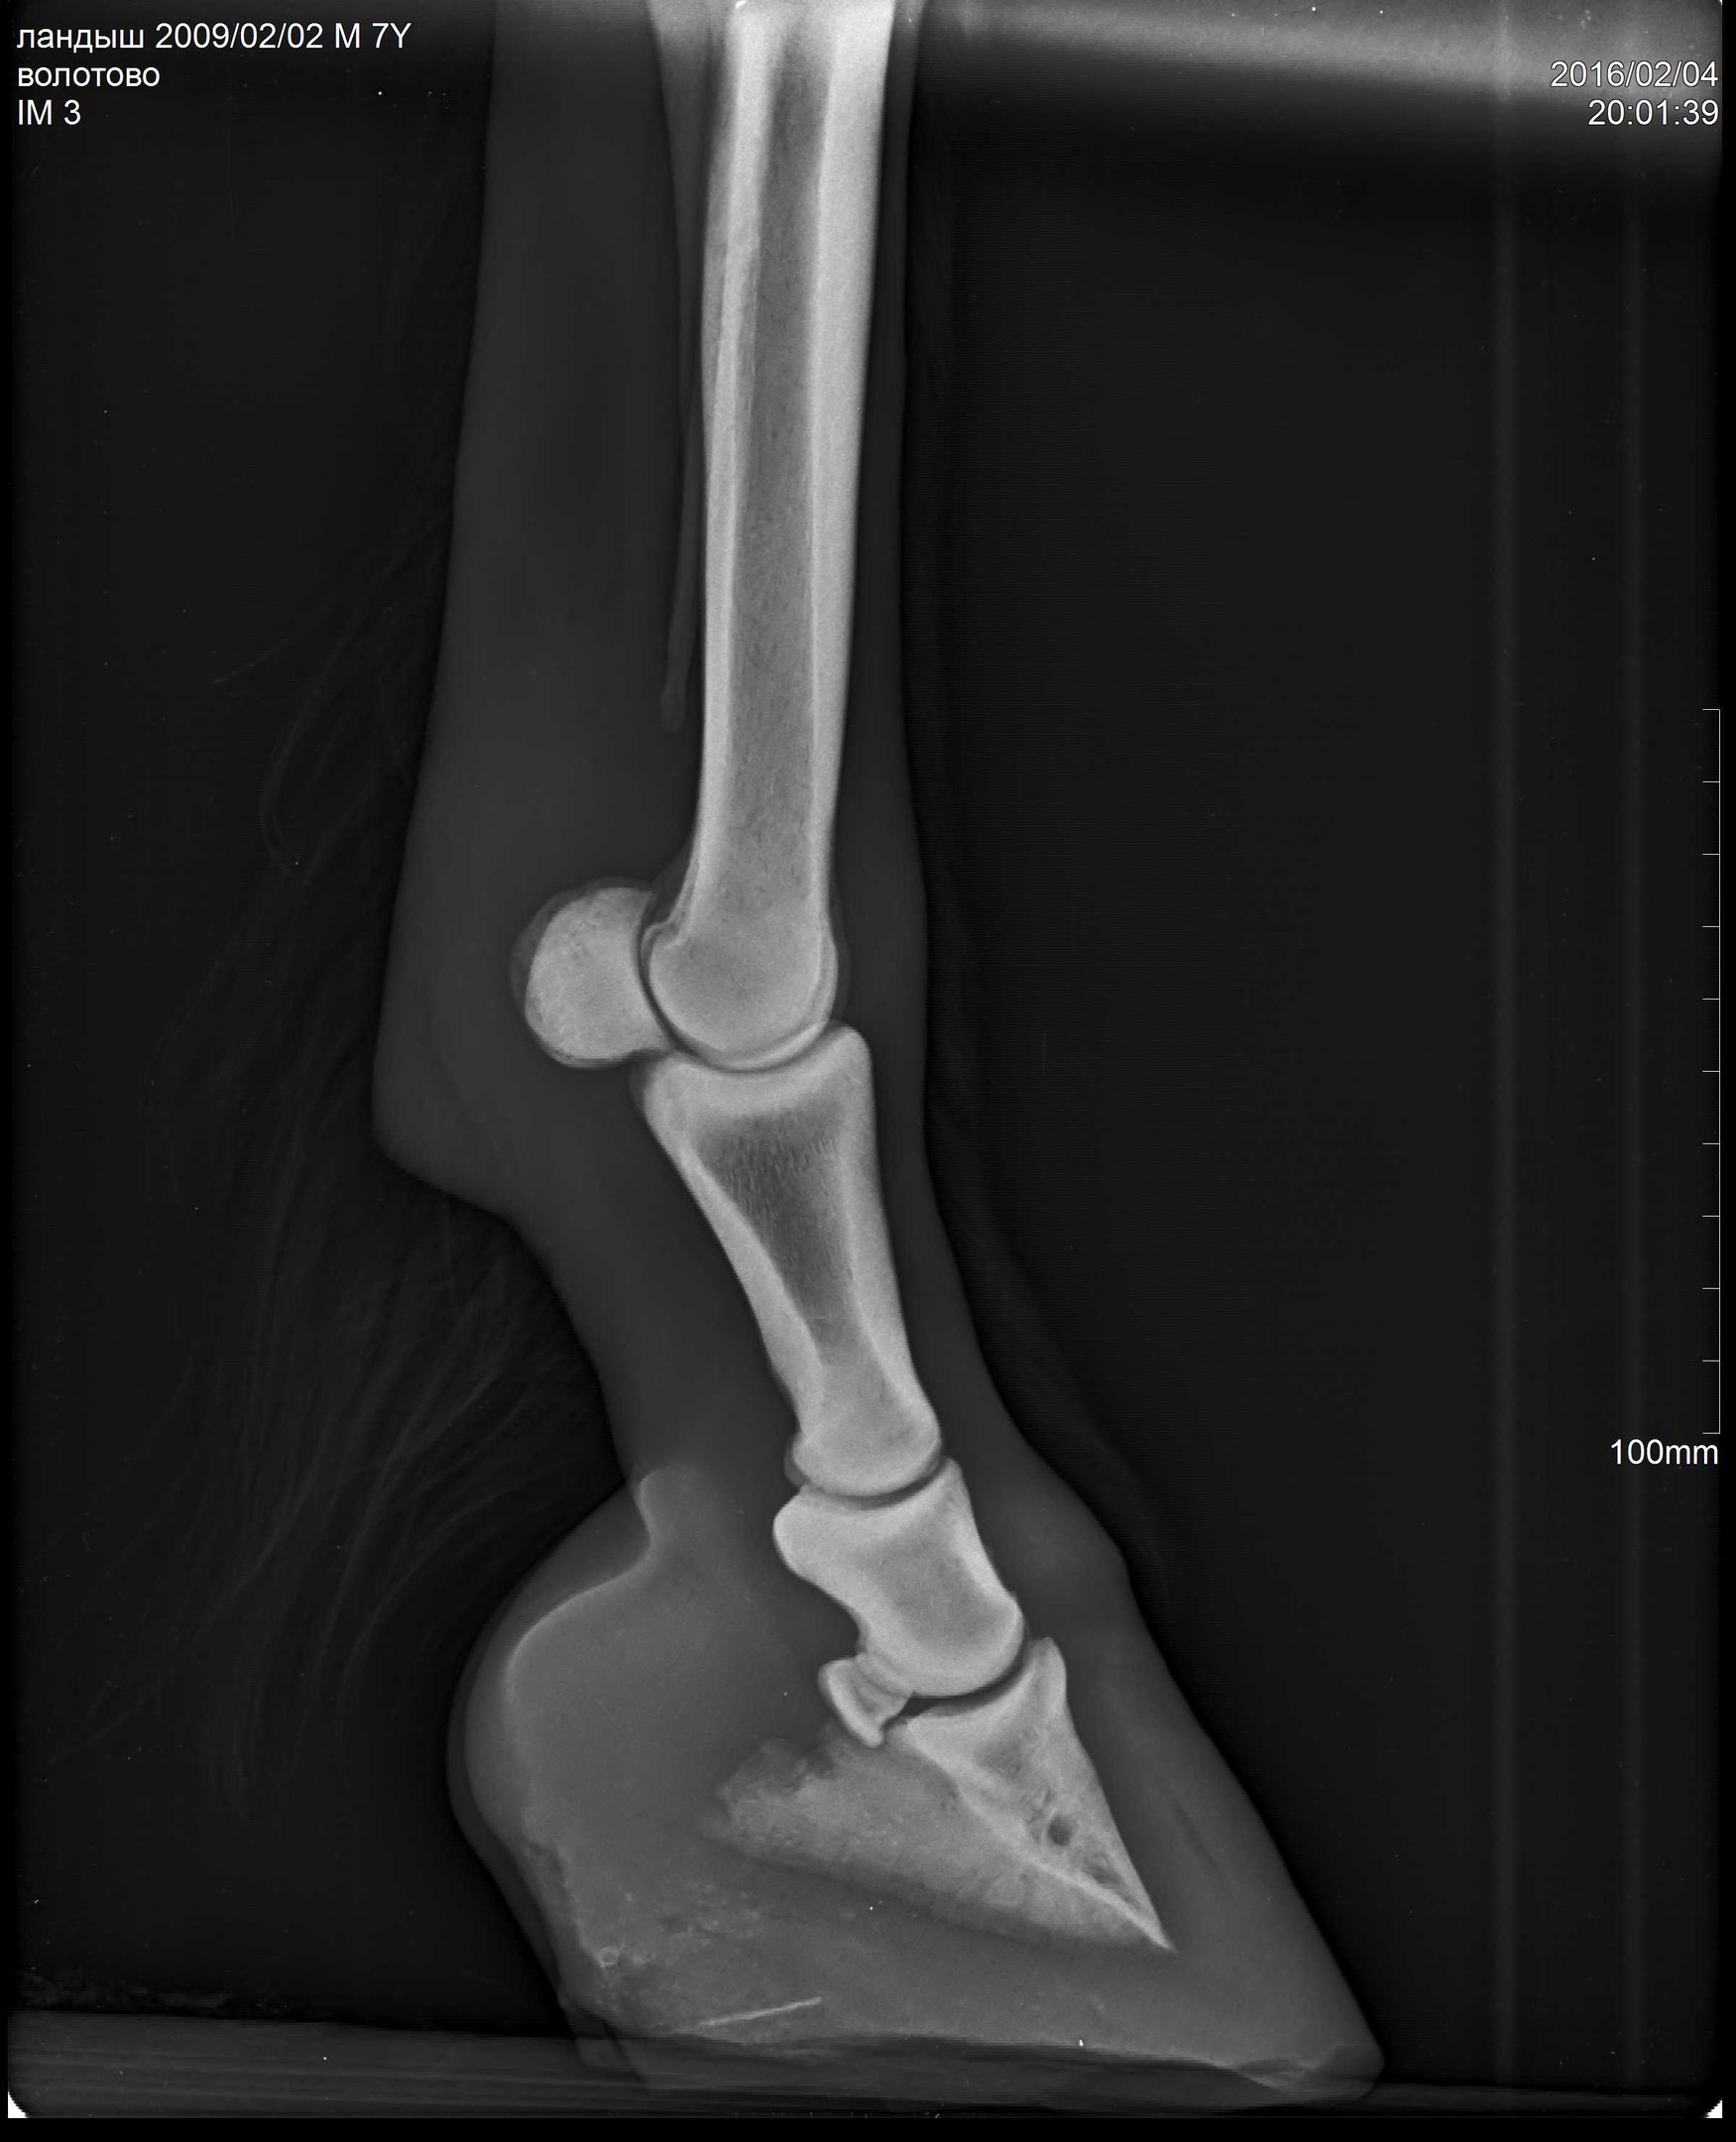

В общем, после чудесного-расчудесного лекарства Флуниджекта и замечательных обнадеживающих рентгенов пони всего лишь требовалась грамотная расчистка. Нужно было чуть изменить угол копыт, чтобы выправить копытную кость более-менее параллельно подошве (хоть в некоторых статьях я читала, что совсем необязательно эта параллельность должна быть нормой).

А тут нужна была тонкая, филигранная работа. Рентгенолог Анна мне оставила диск с программой, где можно было выверять углы, каждый миллиметр контролировать!!!! А я, конечно, со своими клещами и целью тупо на 1см понизить пятки, натворила дел (((